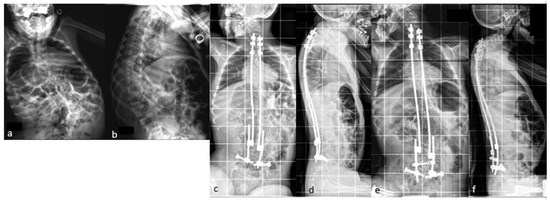

This technique can be considered as a real alternative to arthrodesis in this population, as compared to other techniques that report 16.6% rod breakage in neuromuscular series [16], 15–42% with TGR in early-onset scoliosis [1,2,3,4,5,6,7,8,9,10,11,12,13,14], and 70% in a cerebral palsy series [17]. It provides satisfactory correction results that remain stable until skeletal maturity, with a reduced rate of mechanical complications (5% of rod fractures in our initial series at 5 years follow up) [25]. Patients at risk of rod fractures include ambulatory patients, those with dystonia, those with a higher BMI, or those with excessive kyphosis. Currently, this complication can be avoided using reinforced four-rod constructs in the lumbar region or throughout the spine in patients with any of these risk factors (Figure 5).

Figure 5. (ad) Pre- and postoperative radiographs of 14-year-old patient with cerebral palsy who underwent surgery with a reinforced lumbar four-rod construct.